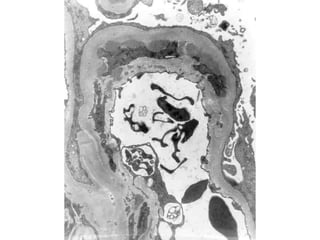

CLASIFICACIÓN

• Histológica

– Glomerulonefritis membranosa

– Glomerulonefritis membranoproliferativa